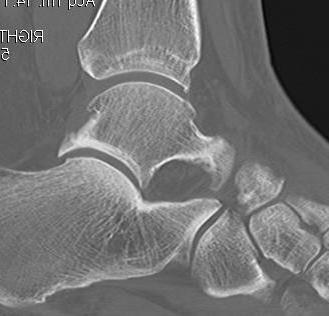

Xray

Anterior tibial and talus spurs with normal joint space